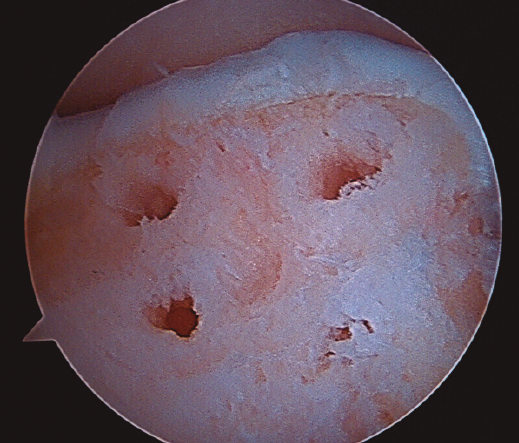

Figura 2. Técnica de estimulación medular con nanofracturas. Obsérvense los bordes del curetaje y la cruentación de la capa mineralizada.

- Posteriormente, realizamos la técnica de estimulación seleccionada entre: brocado o microperforaciones o nanoperforaciones. Preferimos realizar estas últimas a perforaciones más grandes que pueden dañar el hueso subcondral u otras técnicas de brocado con agujas de Kirschner que pueden producir necrosis inducida por el efecto térmico (Figura 2). Cada “nanofractura” debe realizarse separada 3-4 mm con una profundidad de 9-10 mm y un diámetro de 1 mm.